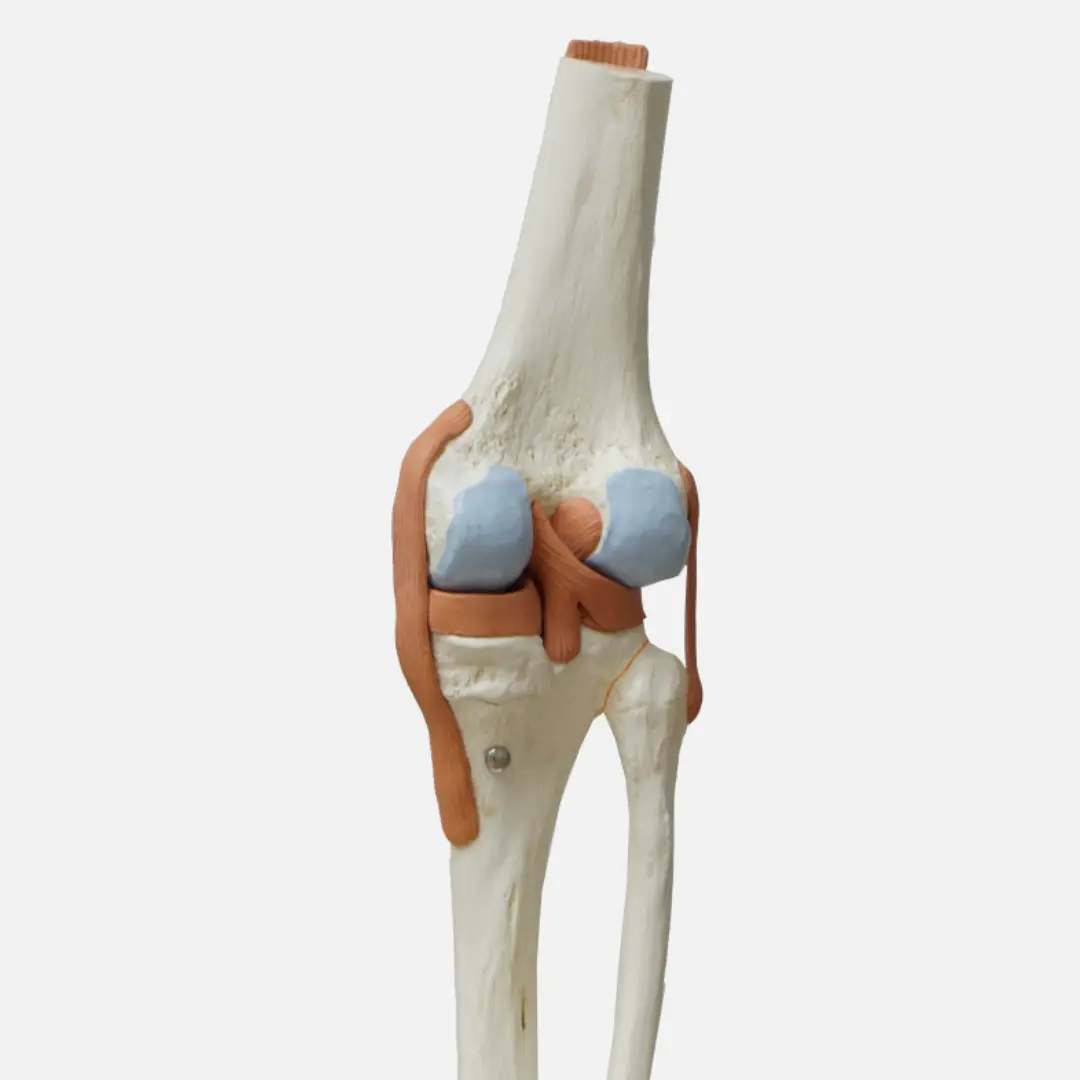

관절 건강에 대한 관심이 높아지면서 콘드로이친이 주목받고 있어요. 콘드로이친은 관절 연골의 주요 구성 성분으로, 관절 건강 유지에 필수적인 역할을 하죠. 콘드로이친 효능부터 건강하게 콘드로이친 복용하는 방법까지 정리해볼게요!

콘드로이친은 다양한 효능을 통해 관절 건강을 지켜줘요.

- 관절 연골 보호:

- 연골의 수분 보유 능력을 높여 연골이 마모되는 것을 막아줘요.

- 연골 세포의 생성과 유지를 도와 관절 기능 개선에 효과적입니다.